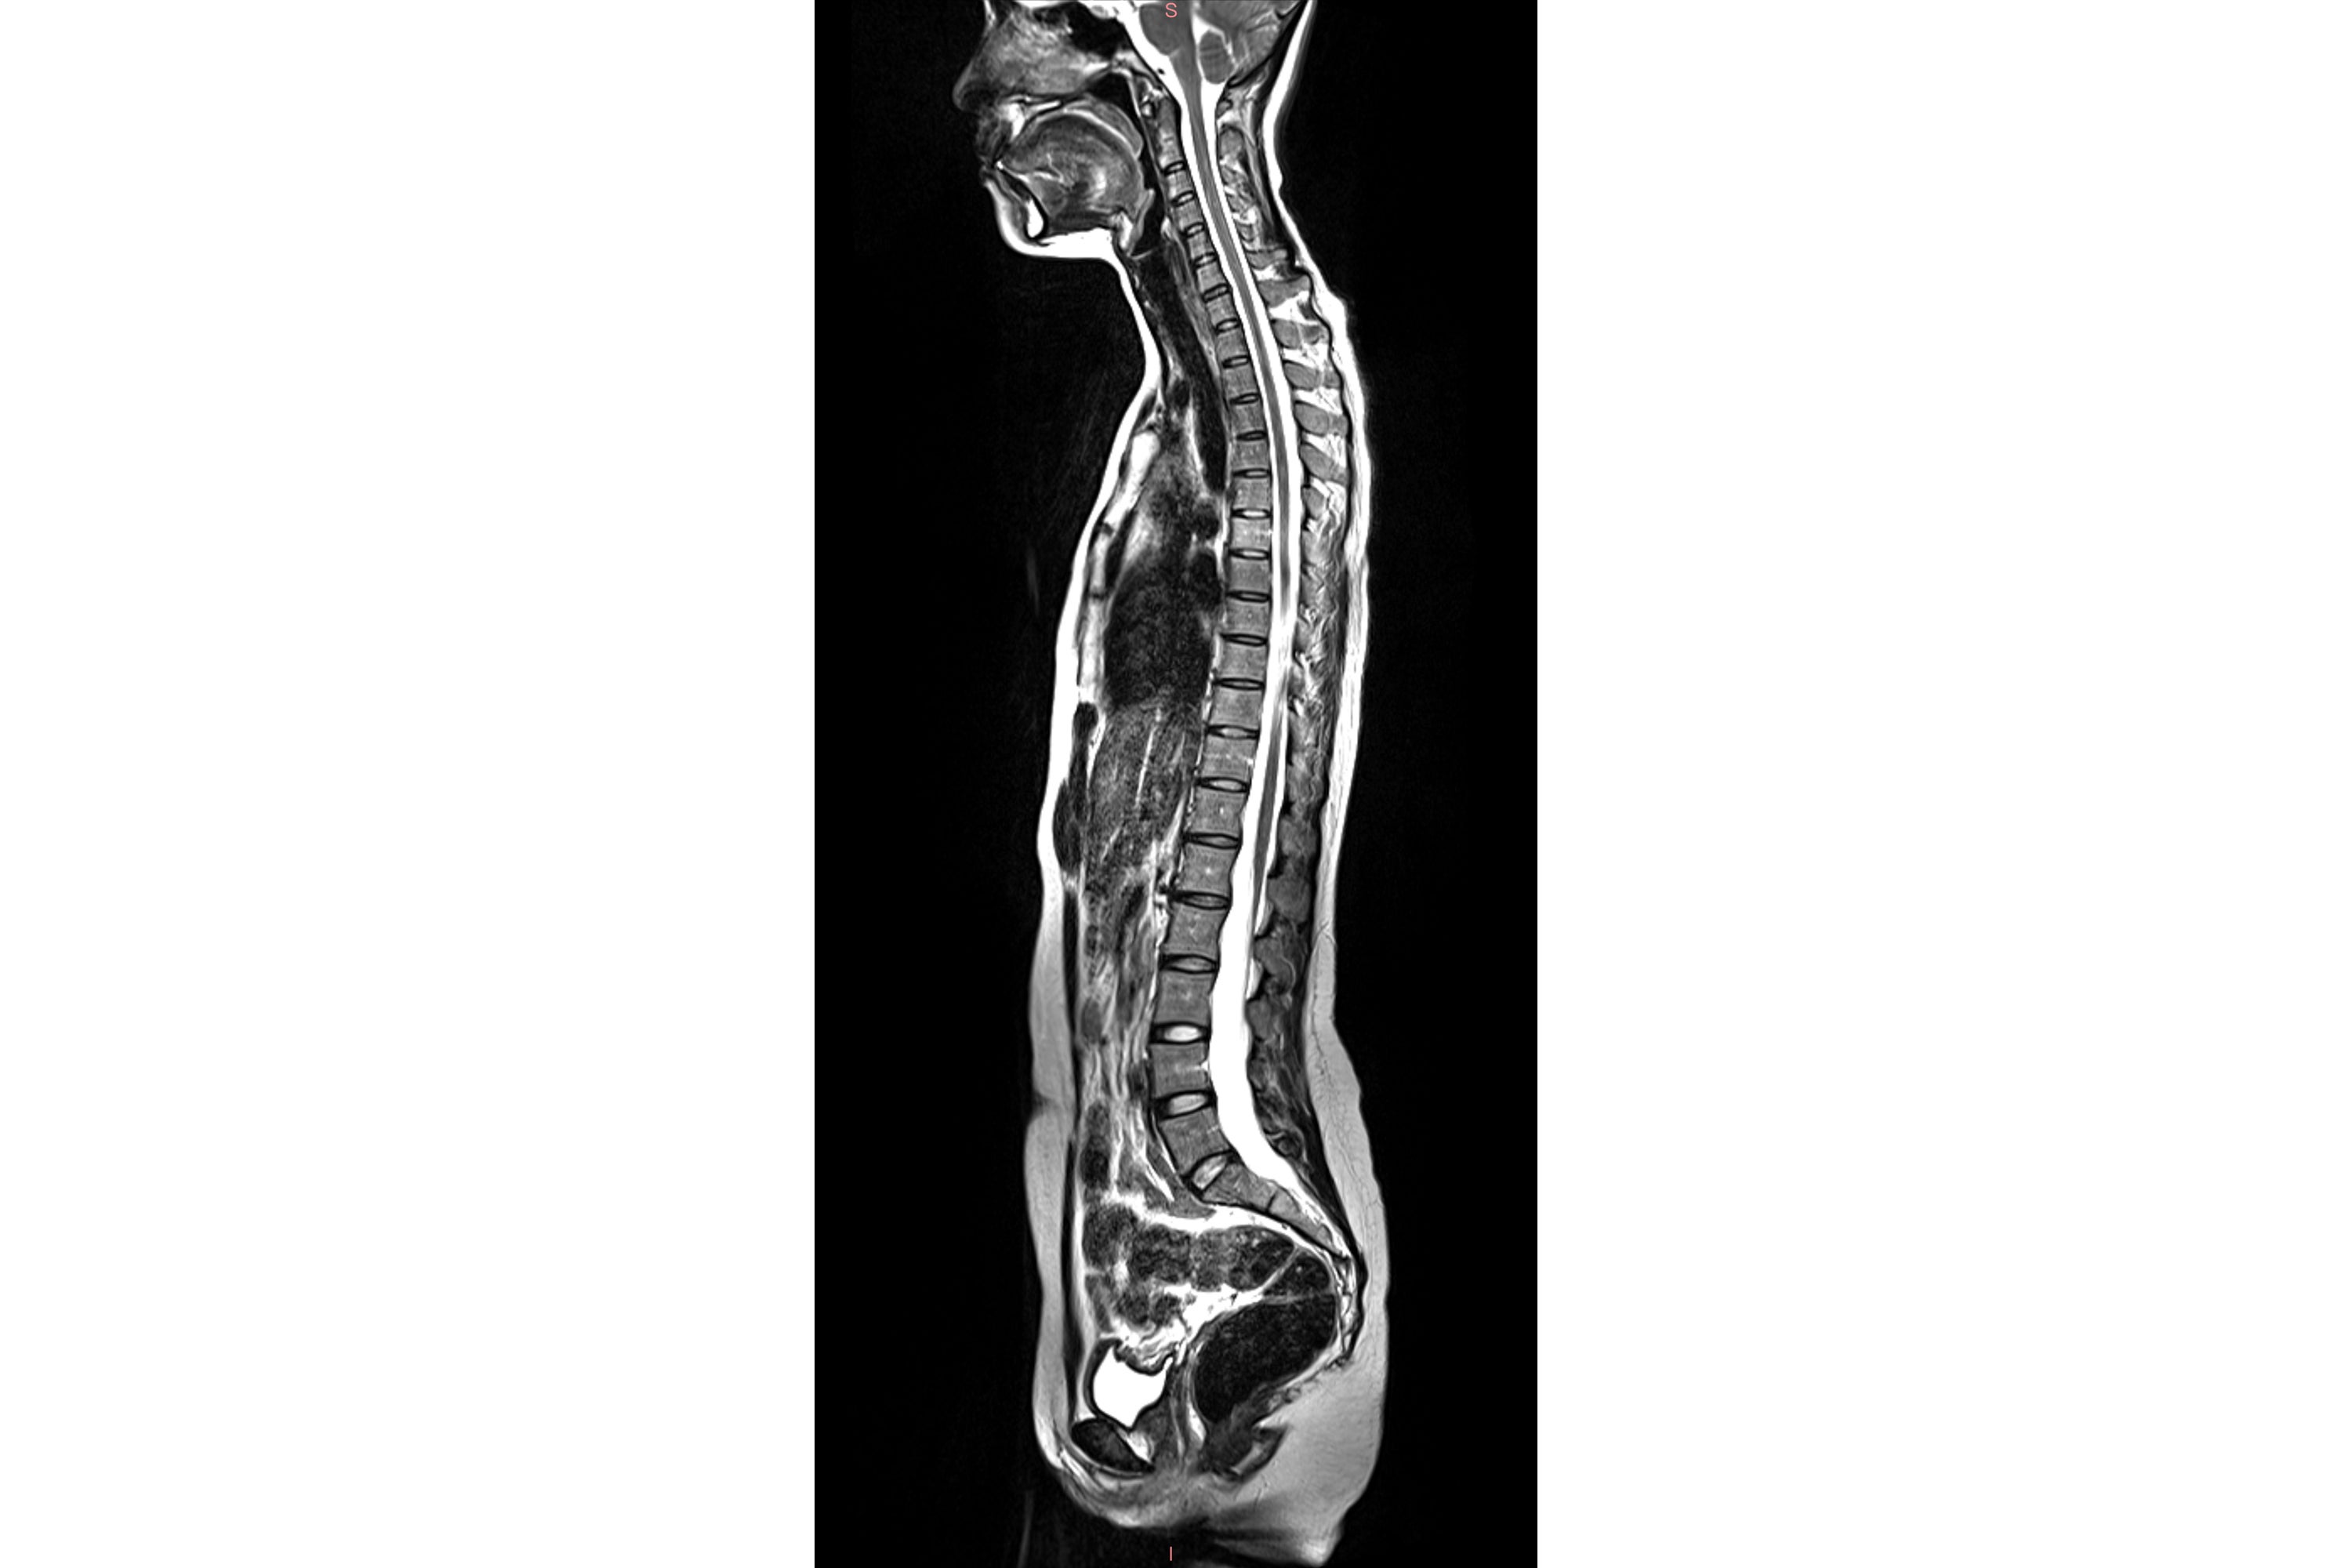

MRI stands for magnetic resonance imaging. It’s a type of medical scan that uses magnetic fields to produce detailed images of organs, bones and other structures inside the body. Unlike many other types of scans, MRIs don't use radiation.

Doctors will order an MRI to help diagnose cancer, brain injuries, damaged blood vessels and other medical conditions. Full-body scans can take an hour or more, with patients lying motionless inside a cylindrical tube.